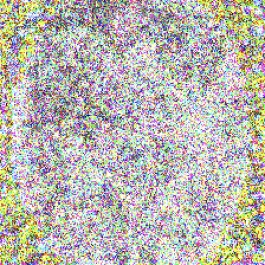

While imperceptible in the final images, the perturbations for dermatoscopic and fundoscopic images were found to carry easily perceptible information about the source image, when the changes were scaled to a range of [0,255]0255[0,255]. In these cases, the adversarial “noise” contained the shape of the lesion or eye. For dermatoscopic images, this shape was in the form of a densely perturbed ring enclosing a sparsely perturbed center (Fig. 8(a)). This phenomenon was most visible when ϵ=0.00125italic-ϵ0.00125\epsilon=0.00125. For the fundoscopic images, this shape was represented by a sparsely perturbed ellipse. In the attacks generated for the model with attention, the shape of this ellipse occasionally diverged from the true shape of the eye (Fig. 8(b)).

(a) Shape of skin lesion found in adversarial “noise”